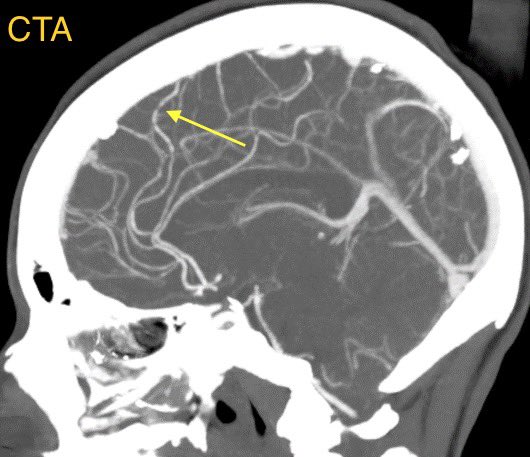

▶️CTA/MRA may show vasospasm